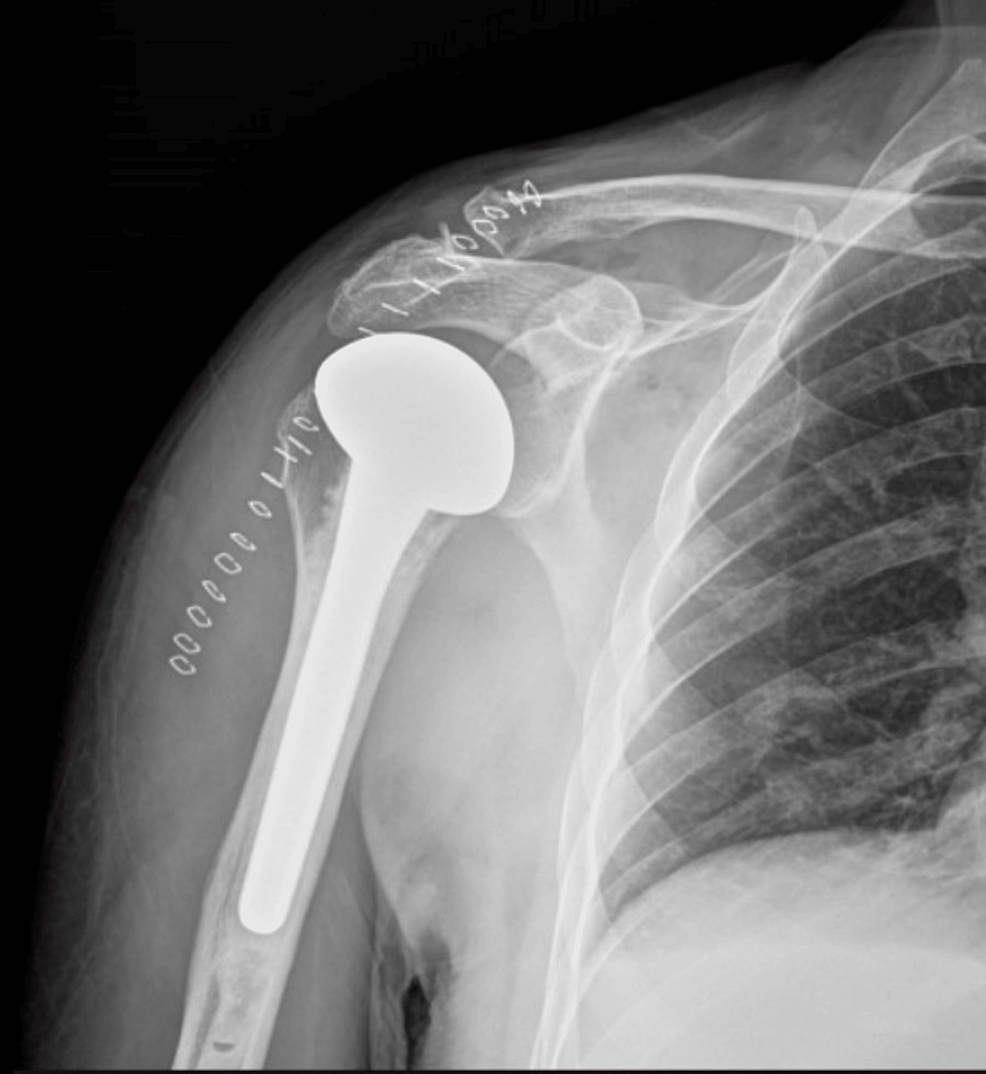

Bulb Sign In Posterior Dislocation . — posterior shoulder instability and dislocations are less common than anterior shoulder instability and dislocations, but are. While the axillary or scapular y. The ‘light bulb sign’ suggests a posterior shoulder dislocation (figure 3). — the light bulb sign refers to the abnormal ap radiograph appearance of the humeral head in posterior shoulder. — posterior dislocation, light bulb sign source: — the current report offers valuable insights regarding the anatomical background of this clinical entity and emphasizes the 'light. — anterior shoulder dislocation. the light bulb sign refers to the abnormal ap radiograph appearance of the humeral head in posterior shoulder dislocation.

The ‘light bulb sign’ suggests a posterior shoulder dislocation (figure 3). — posterior shoulder instability and dislocations are less common than anterior shoulder instability and dislocations, but are. — anterior shoulder dislocation. the light bulb sign refers to the abnormal ap radiograph appearance of the humeral head in posterior shoulder dislocation. While the axillary or scapular y. — the light bulb sign refers to the abnormal ap radiograph appearance of the humeral head in posterior shoulder. — the current report offers valuable insights regarding the anatomical background of this clinical entity and emphasizes the 'light. — posterior dislocation, light bulb sign source: